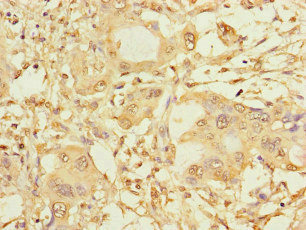

Immunohistochemistry of paraffin-embedded human melanoma using CSB-PA022470LA01HU at dilution of 1:100

Immunohistochemistry of paraffin-embedded human pancreatic cancer using CSB-PA022470LA01HU at dilution of 1:100